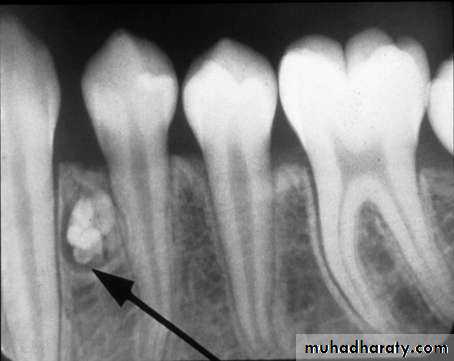

• Cementoblastoma

• Radiography:• Typically appears as radio opaque rounded mass with thin radiolucent margin.

• Attached to the root.

• Resorption of the related root is common.